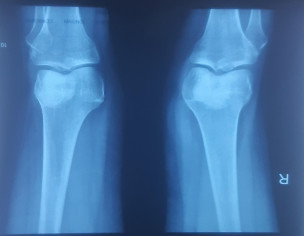

Talk to Orthopedic Surgeon on Knee Tibia Sprain Avulsion Fracture

Aoa ,4 weeks before m stairs se gir gae the, right knee ka fracture hva h ,docter ne kacha plaster 4 week k bad remove krne ko kha h,but plaster remove hone k bad same pain first day k tarah h,but docter khe rahe k koi problem n h,knee bend n ho raha h,kindly xray dekh kr guide kr de, blood report b h thanks

there is iron deficiency anemia and possible infection . may be post traumatic sequalae. also possibility of tibial plateau fracture. which needs further confirmation via examination and immobilization in cast.

Aoa,tibial plateau fracture recovery m Kitna time lgta h,koi zada issue to n h, surgery etc,immobilized kitne weeks k lea h.aur movement start kr de k abi n.

it takes 4 to 6 weeks to heel depending upon circumstances. surgery is not usually required unless there is ligament injury . which is determined later via mri.

decision to start movement depends upon time since injury and pain at the moment. no single answer can suffice.